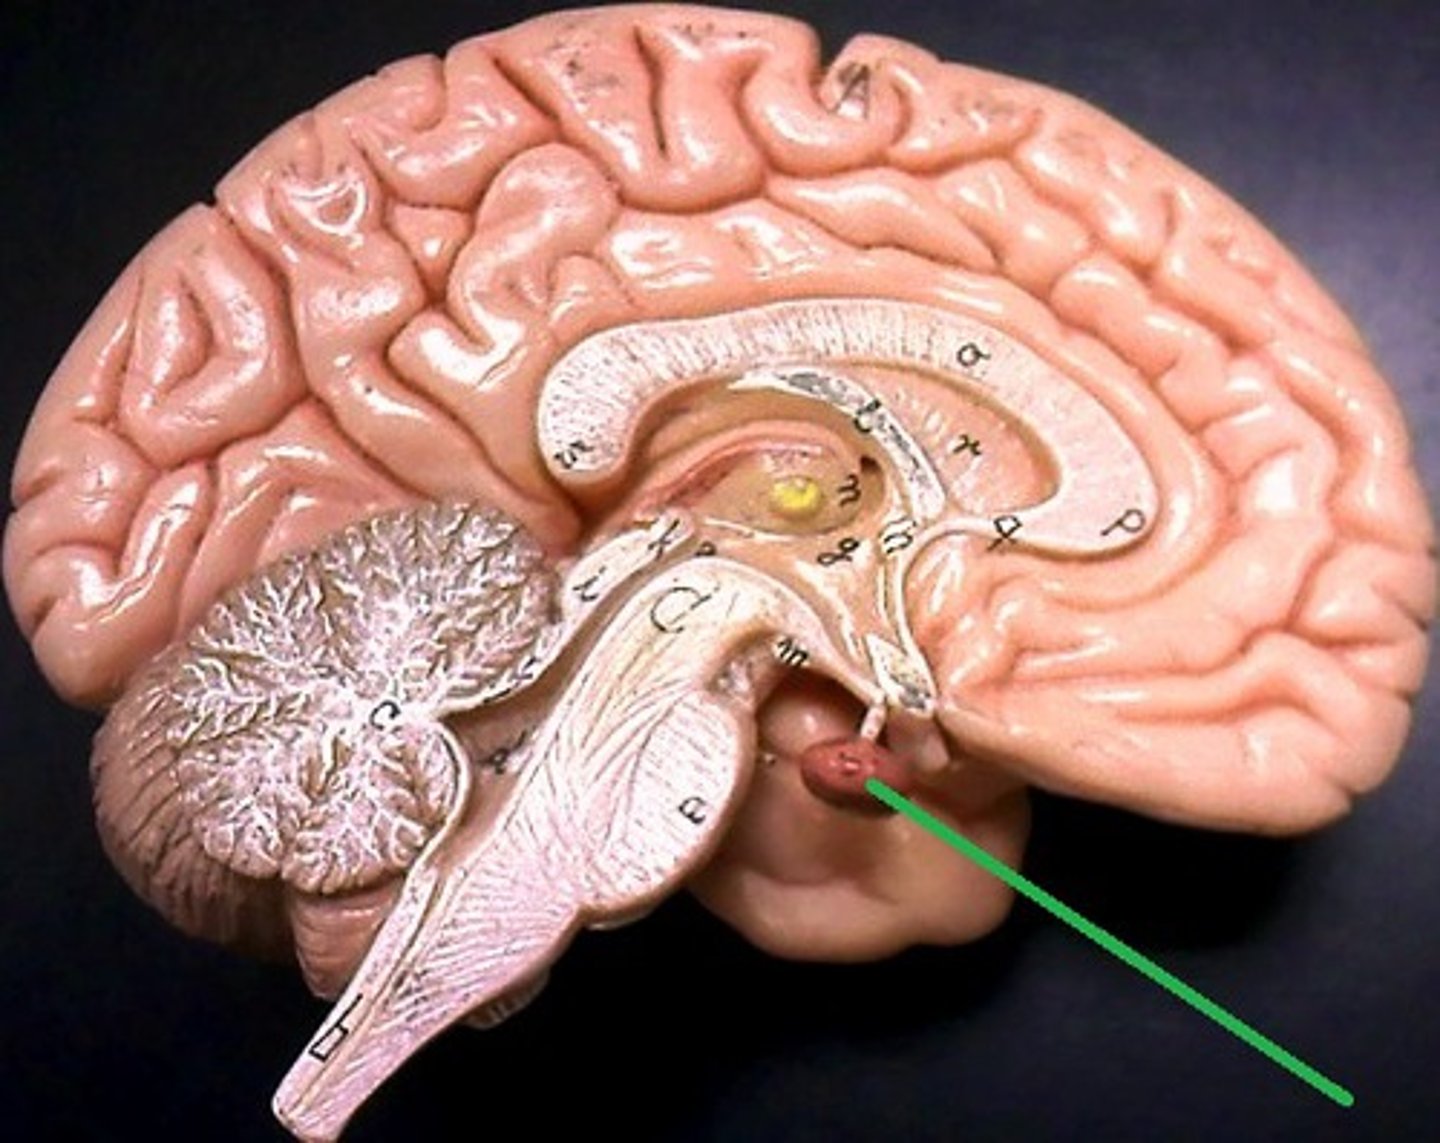

pituitary gland

the thing it hangs from is the infundibulum (the stalk that it hangs from. It regulates hormones. Releases hormones that control other endocrine glands. Releases tropic hormones.

infundibulum

The stalk that the pituitary gland hangs from.

mammillary bodies

two bumbs between pituitary gland and brain stem. Part of limbic system. Contributes to functioning of limbic system.

pineal body

considered an endocrine gland. Secretes melatonin. Plays a role in circadian rhythm - regulation of this. Sleep/wake cycles or night/day cycles. They don't know exactly how this works, but if the pineal gland does not release melatonin, you can have differences in circadian rhythm.

brain stem

Includes the mid brain, pons, and medulla oblongata.

midbrain

corpora quadrigemina,connector of cerebrum, diencephalon, and cerebellum to spinal cord. Connector in central nervous system.

corpora quadrigemina

Also known as the tectal plate. Consists of the superior colliculi and the inferior colliculi.

superior colliculi

bumby part on opposite side of pituitary gland. Top one. Responsible for visual reflex (track objects visually). If we see something in peripheray, we can turn towards object. Instinctive reflex.

inferior colliculi

bumpy part on opposite of pituitary gland. Bottom one. 31 auditory tracking. If we hear a loud noise, we can move toward it.

pons

contains parts of respiratory center. Plays a role in controlling breathing rate and depth.

medulla oblongata

has a cardiac center. Plays a role in influencing heart rate and the force of the contractions in the heart. In response to changes in blood pressure and oxygen levels.

- vasomotor center - helps to control blood pressure. Sends out signals that causes vasoconstriction or vasodilation of blood vessels. Contains parts of respiratory center.

- initiates inspiration and respiration.

cerebellum

cerebellar hemispheres, cerebellar cortex, and arbor vitae.-

the little brain.

- Function: coordinates all voluntary movements. Ability to ride a bike, dance, anything complicated that calls for coordinating movement between left and right sides with skeletal muscles.

- Ability to move joints in a coordinated fashion- cerebellum in charge.

ventricles

cavities in the brain. Includes lateral ventricles - right and left, third ventricle, fourth ventricle, cerebral aqueduct, and choroid plexus.

lateral ventricles (left and right)

right and left. Actual open space. Behind the corpus collosum.

- Cerebrospinal fluid circulates through these ventricles and underneath the meninges.

- Gives the brain buoyancy.

- brain floats a little bit and this prevents trauma.

third ventricle

in the area where the hypothalamus is.

fourth ventricle

located beneath the arbor vitae in the cerebellum.

cerebral aqueduct

connector between third and fourth ventricle in front of colliculi.

choroid plexus

ependymal cells - line ventricles and central canal of spinal cord.